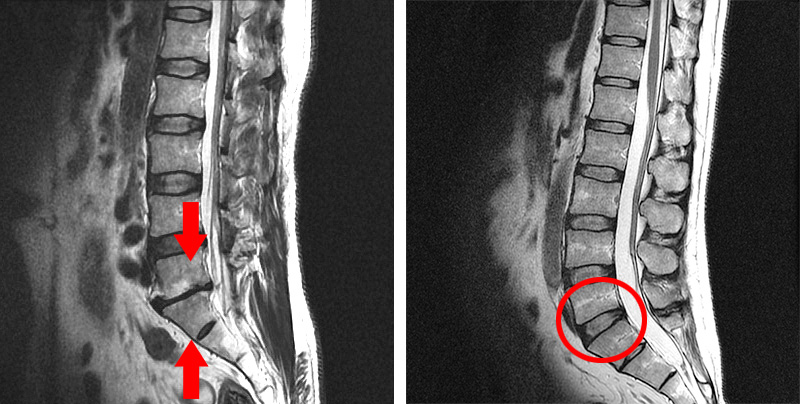

• 간격이 좁아진 디스크

• 정상 디스크

첫 번째 경우는 X-ray나 MRI 검사결과를 보고 디스크의 높이가 낮아진 것을 협착이라고 착각하는 경우입니다. 디스크가 퇴행되었거나 또는 디스크가 탈출되어 수핵이 빠져나가면 디스크의 높이가 낮아지는데, 디스크의 높이가 낮아지면 '디스크가 눌려서 압착되어 있으니까 이게 협착이구나' 하고 착각하게 되는 것 같습니다. 사실 협착이라는 단어는 일상생활에서 잘 쓰지 않는 단어이기 때문에 눌려서 압착되어 있는 걸 협착이라고 오해하는 것이죠. 그러나 디스크에 퇴행성 변화가 발생하여 디스크의 높이가 낮아진 것은 협착이 아니라, 그냥 허리디스크입니다. 협착이라는 것은 디스크를 옆에서 봤을 때 디스크가 눌린 게 아니고, 척추관이 좁아진 것을 말합니다.

• 좁아진 척추관

• 정상 척추관

척추관이 좁아지게 되면 MRI로도 많이 좁아진 게 보이며, 반대로 협착증이 아닌 경우에는 MRI 상으로도 공간이 넓습니다. 따라서 단순히 디스크의 높이가 낮아진 것을 보고 이걸 협착이라고 착각하시면 안 됩니다.